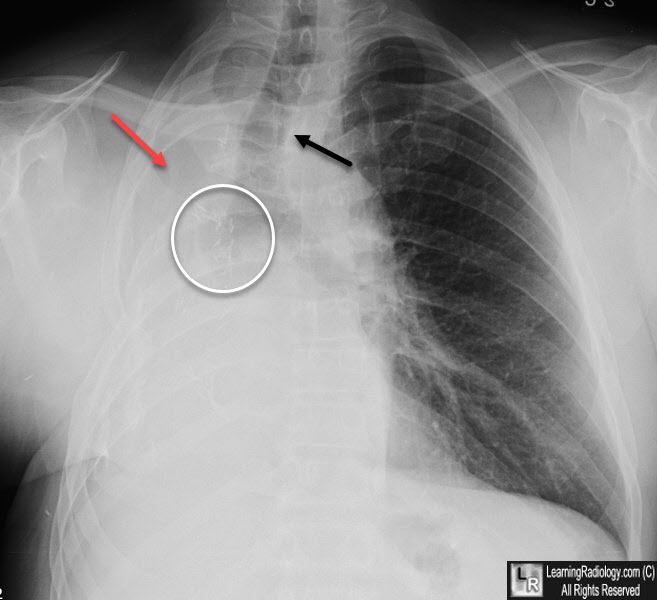

What is going on in this radiograph of a post-operative patient?

A couple things

Firstly, the aortic notch and mediastinum appear shifted to the left, but that is because this patient had a left sided wedge lung resection, so it is not indicative of aortic dissection.

There is an opacity behind the heart and we can no longer see the left hemidiaphragm. This is a common post-operative finding due to atelectasis of the lower lobe, but may also occur in the setting of a lower lobe pnemonia or left sided pleural effusion.

“Left lower lobe atelectasis/consolidation and/or effusion” is often the diagnosis